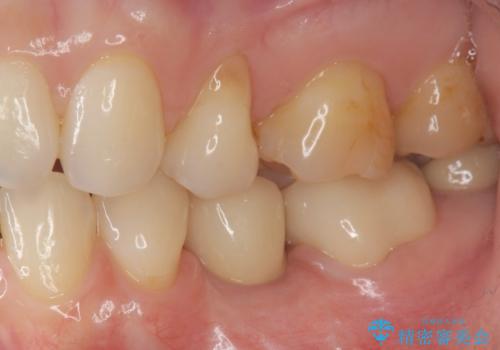

生まれつき永久歯の欠損がある場合、乳歯が大人になっても残っている場合があります。

残念ながらぐらつきが大きくなり、残すことが難しくなり抜去したのちインプラントを用いて咬合機能の回復をしっかりと行いました。